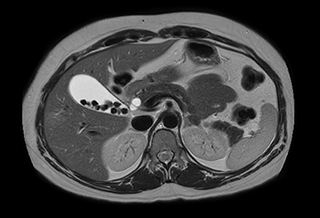

Performed on Ingenia Ambition. FOV 430 mm, voxels 1.3 x 1.3 x3.0 mm, 130 slices, Breath hold 16.6 sec

Using mDIXON provides excellent fat saturation uniformity. No artifacts seen at the edges in these images, while these were quite commonly seen with eTHRIVE on our previous system. Note also the high resolution.

Ingenia Ambition, 3D breath hold, FOV 370 mm, voxels 1.51 x 1.58 x 4.0 mm, 120 slices, scan time 19.6 sec.